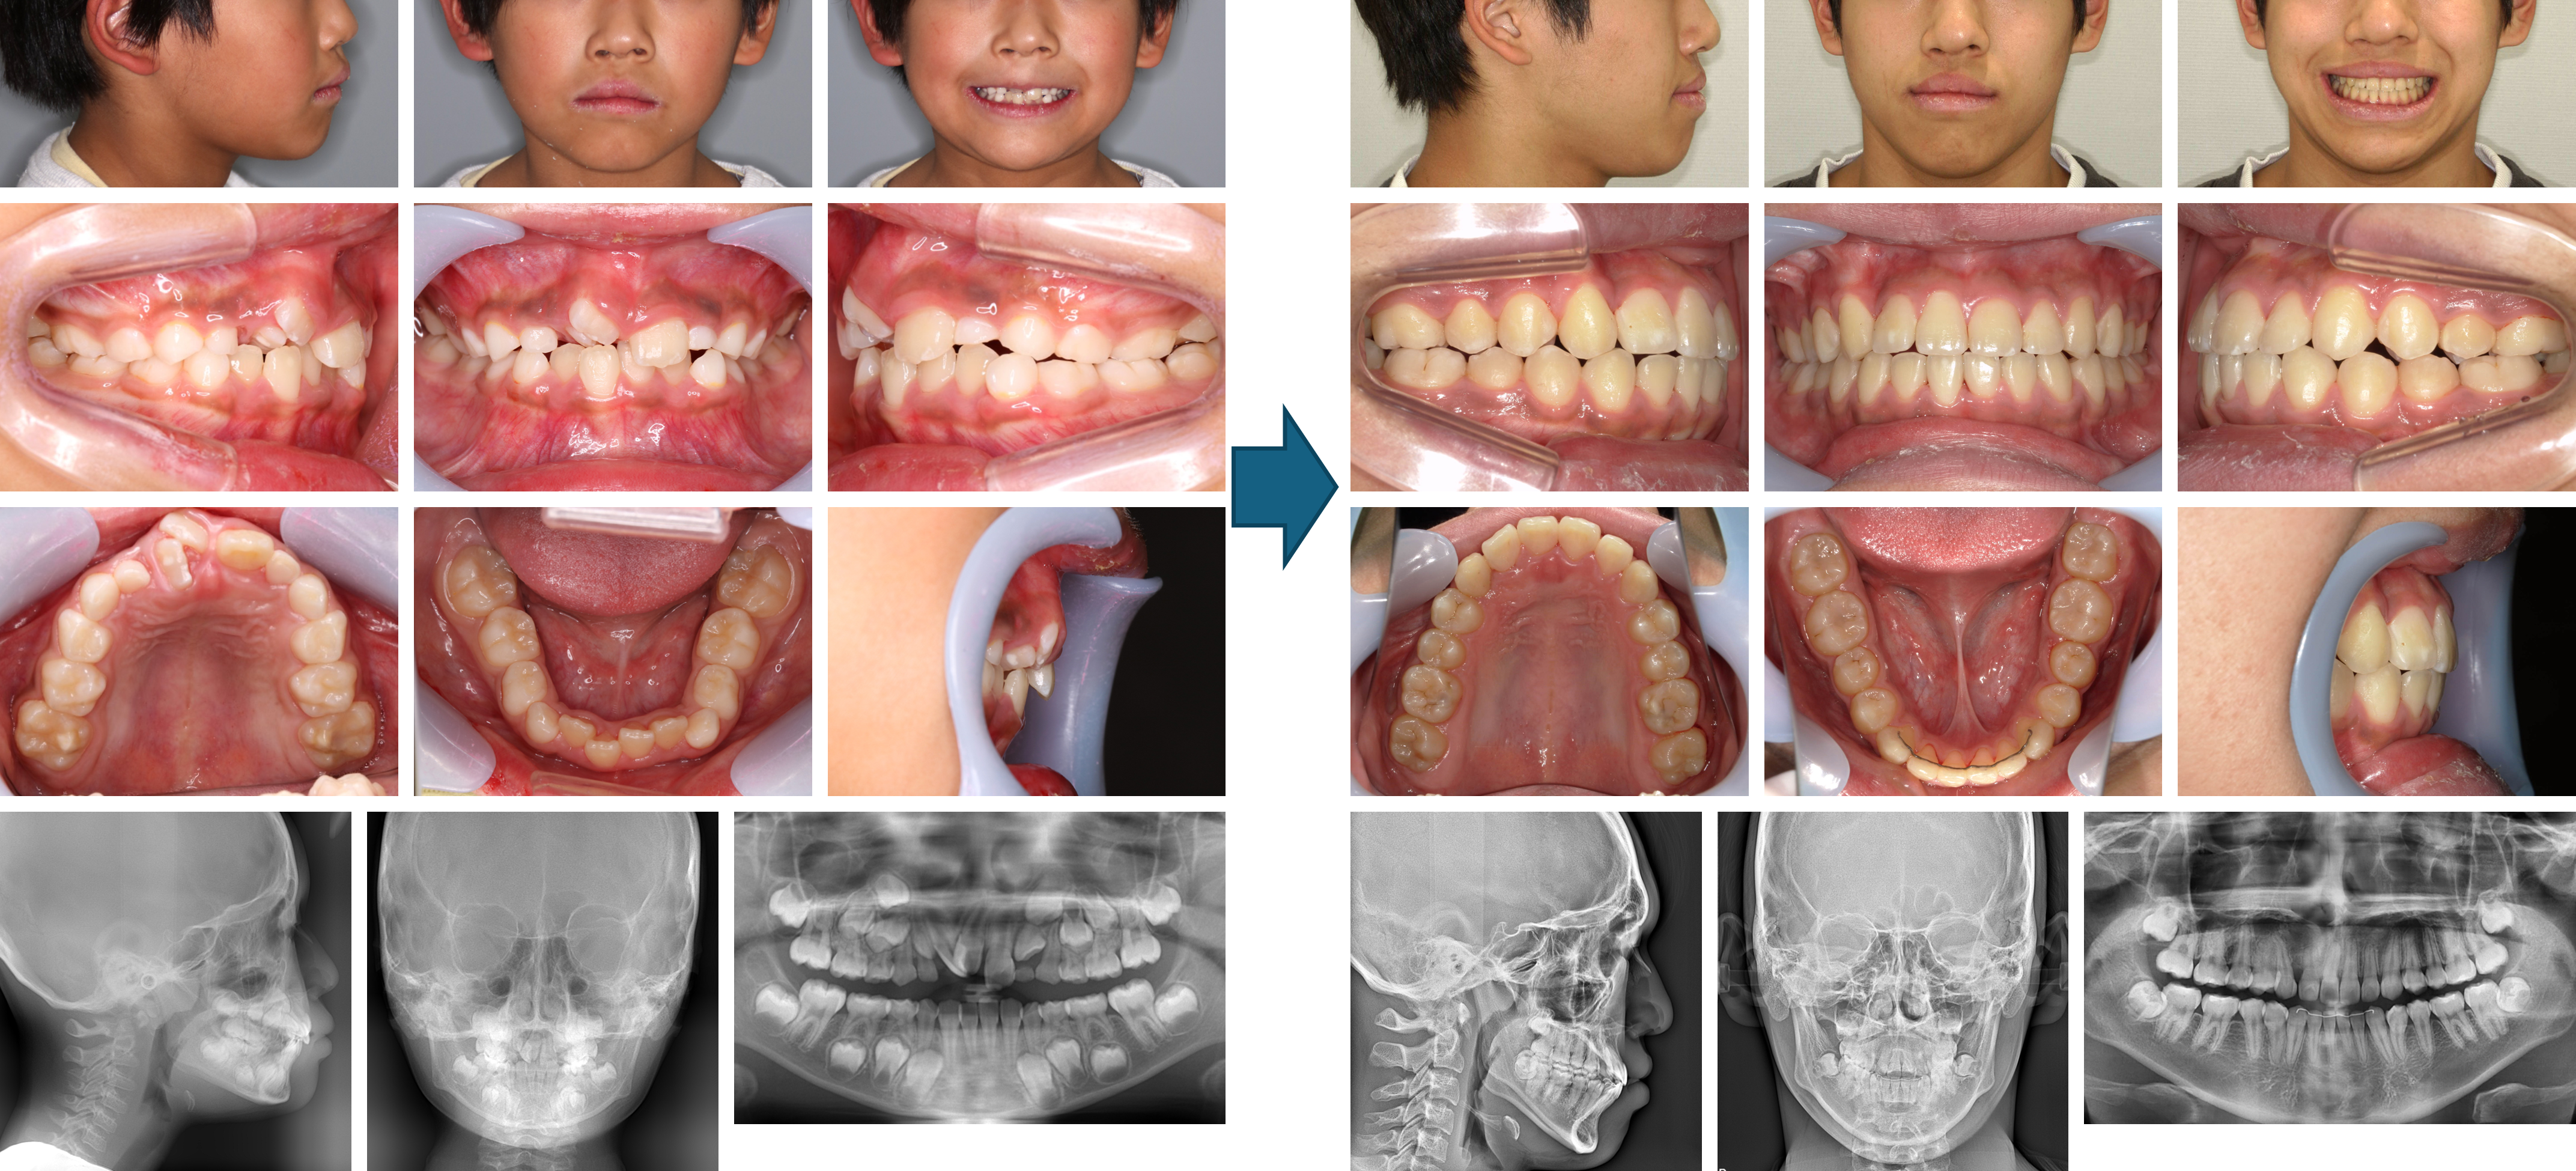

【治療例 K6893】初診時年齢:6歳11か月 / 性別:男性 / 主訴:ガタガタ、大人の歯が生えてこない

主訴:ガタガタ、大人の歯が生えてこない

診断名:非抜歯叢生症例

使用した主な装置:ヘッドギア、マルチブラケット装置、顎間ゴム

抜歯/非抜歯および抜歯部位:非抜歯

治療期間:5年5か月

治療回数:48回